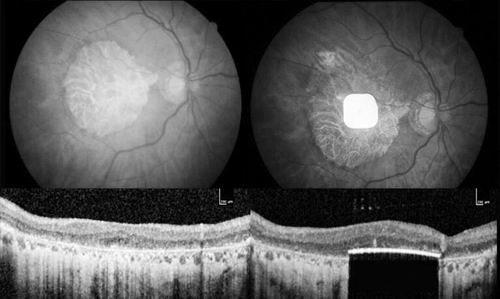

一款植入视网膜下的电子设备可为AMD患者恢复部分视力。

本报讯 科学家使用一种眼部植入物改善了数十名失明的老年性黄斑变性(AMD)患者的视力。这种2毫米×2毫米的植入物仅30微米厚,可通过手术植入视网膜下,取代受损的光敏细胞。

在当前的研究中,38名受试者在5个欧洲国家的17个临床中心接受治疗,其中32人在植入一年后接受了测试。有26人的视力有临床意义的改善——能够在标准视力测试表上看清两行字母。总体而言,大多数参与者的视力水平已经接近PRIMA所能达到的分辨率。